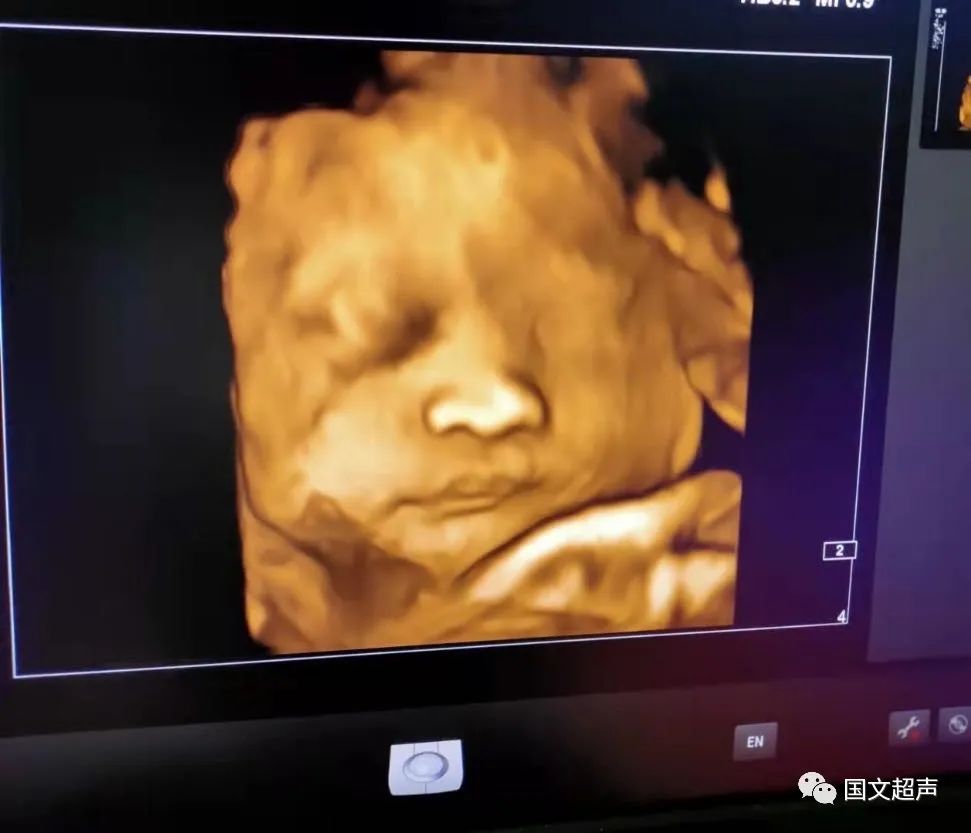

一.飛利浦EPIQ7高端四維彩超

我院目前使用的是飛利浦EPIQ7高端四維彩超,它擁有高品質自動成像分析技術,分辨率及清晰度高,可以較清晰的顯示宮內胎兒的生長發(fā)育情況,為診斷胎兒先天性畸形,如唇裂、脊柱裂、顱腦發(fā)育異常、骨骼發(fā)育異常、心血管畸形等提供準確的科學依據。